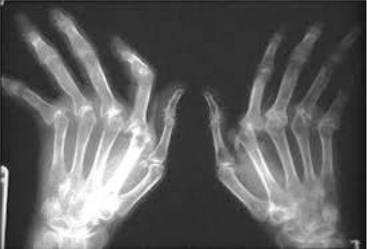

При осмотре: пониженного питания. Кожа бледная, тургор снижен. На разгибательной поверхности локтевых суставов - округлые плотные образования d=1-2 см, безболезненные при пальпации. С обеих сторон пальпируются увеличенные подчелюстные, подмышечные лимфоузлы, умеренно плотные, безболезненные. Атрофия мышц тыльных поверхностей кистей. Определяется припухлость и болезненность при пальпации II-IV пястно-фаланговых и II-III проксимальных межфаланговых суставов, переразгибание во II-III дистальных, сгибательная контрактура II-III проксимальных межфаланговых суставов с обеих сторон. Объѐм активных движений в указанных суставах снижен. Ульнарная девиация кистей. По внутренним органам – без патологии.

Рентгенограмма кистей.